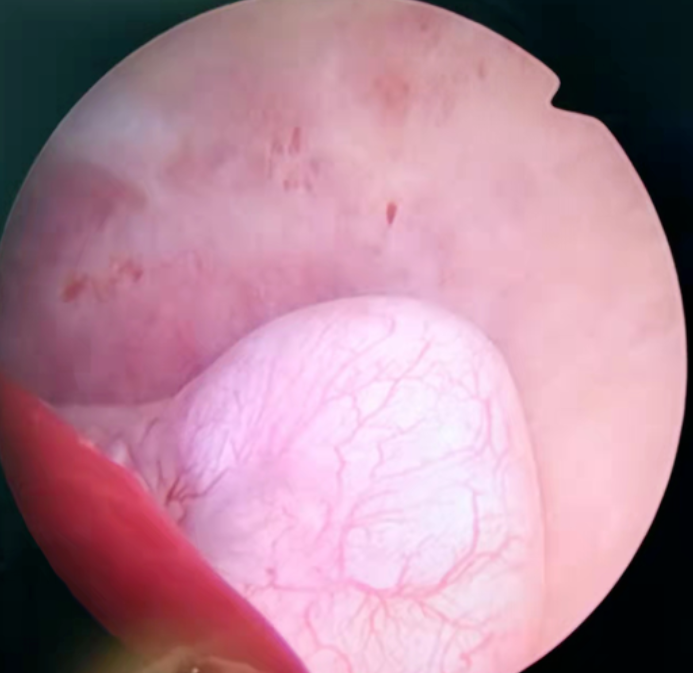

入院后在基础麻醉下行宫腔镜检查术。术中探查:探宫腔深8cm,宫腔形态基本规则,子宫后壁可见一直径约1.5cm肌瘤凸向宫腔,双侧输卵管开口可见。